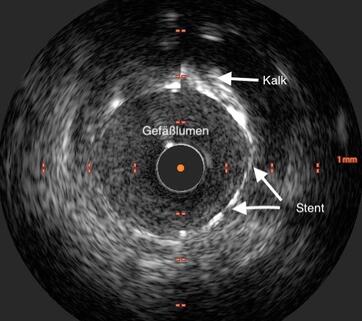

Der intravaskuläre Ultraschall (das heißt „innerhalb

des Blutgefäßes“) wird mithilfe eines

speziellen Ultraschallkatheters durchgeführt.

Der

Gefäßultraschall liefert dem Arzt wichtige Zusatzinformationen zur Behandlung von

Erkrankung wie beispielsweise einer Dissektion (Einrisses) der Gefäßinnenwand.

Unter den heute verfügbaren Untersuchungsmethoden ist der Gefäßultraschall die

Methode mit der höchsten Genauigkeit.

Die Gefäßultraschalluntersuchung wird im Rahmen einer Linksherzkatheteruntersuchung durchgeführt. Ein dünner Draht wird in die Herzkranzarterie eingelegt. Dieser Draht dient, ähnlich wie bei der Ballonaufdehnung als Leitschiene für den Ultraschallkatheter. Ein dünner Kunststoffkatheter mit einem Durchmesser von ca. 1mm, an dessen Ende sich eine sehr kleine Ultraschallsonde befindet. Diese wird in die Herzkranzarterie eingeführt.

Die Ultraschallsonde liefert Bilder aus dem Inneren der Herzkranzarterie und zeigt alle Wandschichten der Arterie in einem Querschnittsbild. Die Auflösung der Ultraschallsonde ist sehr hoch, kann damit neben kleinsten Ablagerungen auch den genauen Ort eines Einrisses in der Gefäßwand zeigen und erlaubt damit eine passgenaue Therapie mittels Stentimplantation.